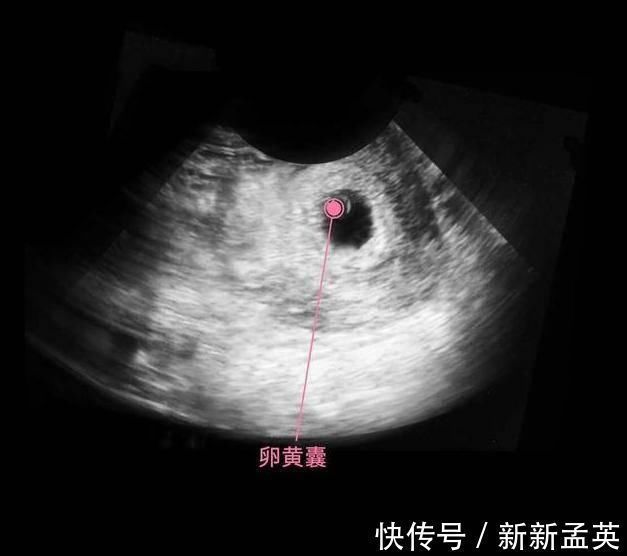

上图可见子宫中的囊状结构,胎儿由两层的组织构成胚胎,所有的器官和组织都是有这些组织发育而成,胚胎羊膜囊的空腔中,开始有羊水积聚,为将来包裹和保护胎儿做准备。

细胞继续分化,有的分化成胎儿的大脑,有的分化成胎儿的肾脏和肝脏,还有的分化成心脏等,这个时期的宝宝叫做胎芽,依靠着卵黄囊提供的营养,还用不到母体的营养呢,所以此时有了怀孕反应,没有食欲也没有关系,对胎儿发育的影响不大。